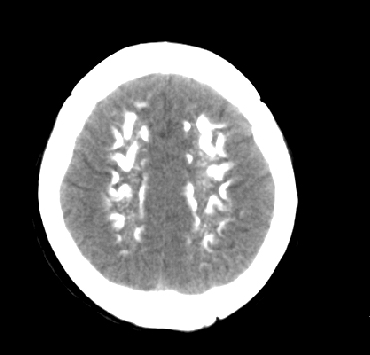

女性 38岁 病人脚弓反张 8岁以后不能行走 今年查pth11.9ng/ml(正常28ng/ml)

这么弥漫的钙化还第一次见。

考虑甲状旁腺功能减退症,该病是因甲状旁腺激素分泌减少或功能障碍所引起的少见病。其特点是低血钙,高血磷,且血pth极低。因低钙常可引起神经精神激惹症状,包括手指,趾,口角麻木,严重时可出现肌肉痉挛,喉哮鸣和惊厥,甚至癫痫样发作,有的可出现抑郁症及精神失常。长期的高磷血症可引起脑内结构对称性多发性钙化,特别是小脑和基底节的钙化可致锥体外系症状,而钙化的ct表现为类似于脑出血的密度增高影。

鉴别诊断:fahr 病,又称特发性家族性脑血管亚铁钙沉着症,是一种少见病,男女发病无显著差异,多为散发。临床表现为阵发性意识不清,首发症状开始于14~51 岁不等,以后呈阵发性发作,表现为突然神志丧失、跌倒、四肢抽搐约,发作后常表现为意识淡漠,性格改变,血清钙在正常范围。ct表现尾状核头呈倒“八”字形或片状钙化,在大脑半卵圆中心皮、髓质交界处多为点、小片状钙化,丘脑多呈对称小点、小条状钙化,小脑齿状核呈括弧形或不对称性小片状钙化。

原发性甲状旁腺功能减退症和fahr病都有神志上的改变等症状,且头颅ct检查均可见颅内出现钙化。但fahr病无pth低下,ct表现钙化影在大脑半卵圆中心皮髓质交界处、丘脑、小脑齿状核等处。 而甲状旁腺功能减退症pth极低,ct虽可见钙化影,但部位在小脑和基底节等处。